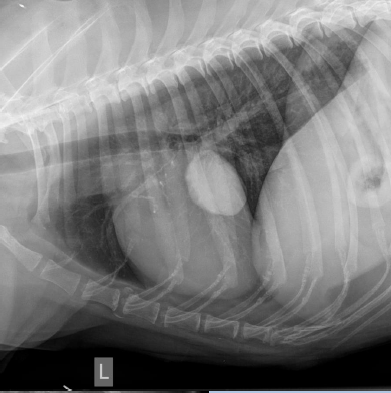

Lateral

2 to 5 left ventricle

5 to 9

Right ventricle

9 to 11

Pulmonary artery

Aortic arch

Right auricle